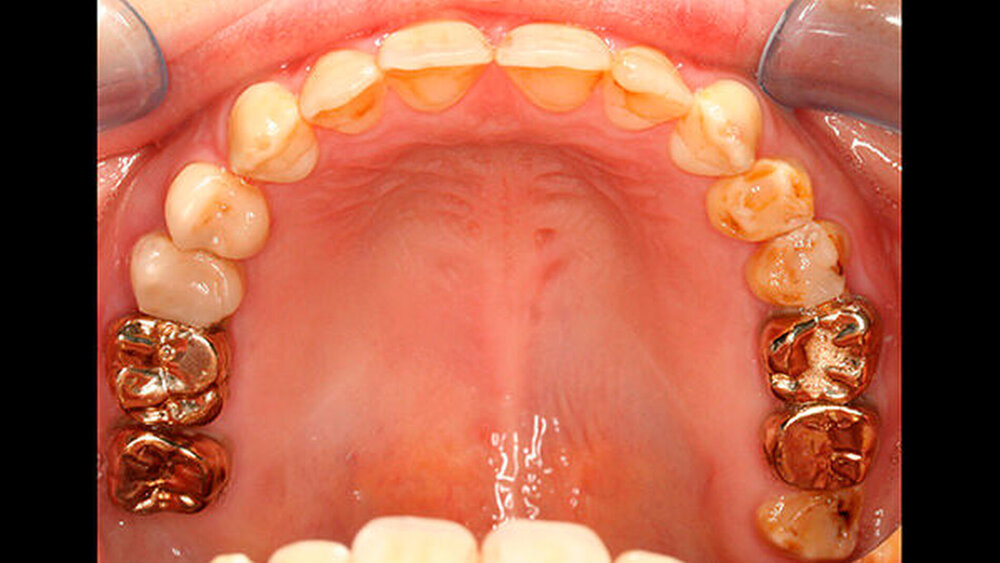

Bisher war die Patientin größtenteils mit provisorischen Maßnahmen behandelt worden. Eine Ausnahme bildeten hier die Sechsjahrmolaren, die ihrzufolge sehr zeitnah nach vollständigem Durchbruch mit Goldteil- beziehungsweise -vollkronen versorgt wurden. Im Oberkiefer wurden später auch für die zweiten bleibenden Molaren Vollkronen gewählt (Abbildungen 1 und 2).

Abbildung 1 gibt einen guten Überblick darüber, dass teils mehrere Restaurationen pro Zahn durchgeführt wurden und die dazwischen verbliebenen Bereiche aus Zahnschmelz oft nur gering waren (insbesondere an den Frontzähnen). Gleichzeitig zeigt aber auch der Vergleich der kontralateralen Prämolaren, wie anfällig dieser verbliebene Schmelz für Abplatzungen war. Im Unterkiefer ist gerade an Zahn 37 deutlich zu erkennen, wie großflächig die Schmelzverluste sein können, wenn auch die Restauration nicht mehr intakt oder vorhanden ist.

Zudem kann es immer wieder zu Abplatzungen des verbliebenen Schmelzes kommen, so dass der entsprechende Zahn eine neue Restauration benötigt, oder die schon vorhandene ausgedehnt werden muss (siehe auch Abbildungen 1 bis 3) [Crawford et al., 2007].